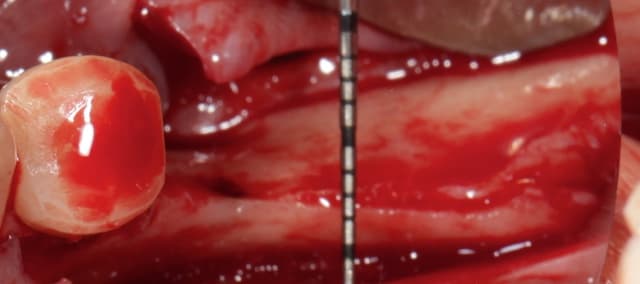

Puisqu'on parlait de ROG verticale, en voici une toute fraiche de ce matin, comblement osseux 50/50 os autogène et Bio-oss le toute recouvert par une membrane PTFE armé titane pinsé.

oui os autogène prelevé avec un scraper zone retromolaire.

A J+7 ça a l'air de bien se présenter.